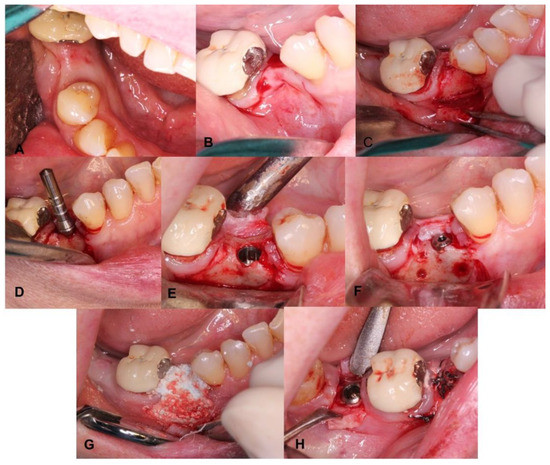

4.5. Patient No.5

| 5 M 64 | NO [-] Sinus lift with lateral window | Yes [No] | G | No | G | No | No |